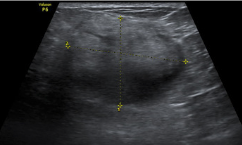

Invasive ductal carcinoma

Adenocarcinoma extending beyond ducts (basement membrane)

• Most common breast cancer (80%)

• Metastasize via blood + lymph

Grades

• 1 (low) = well-differentiated (less likely to spread)

• 2 (moderate)

• 3 (high) = poorly differentiated (likely to spread)

Present:

• Hard immobile mass

• 50-60yrs

• African Americans

Treatment:

• Lumpectomy

• Mastectomy (partial/ total)

• Radical mastectomy (includes muscle + lymph nodes)

• Chemotherapy

• Radiation

• Hormonal therapy (tamoxifen)

• *Hypoechoic mass**

• Ill-defined

• Hyperechoic angular margins

• Spiculations or thick halo

• Ductal extension

• Branched pattern

• Microcalcifications

• Vascular

Non-compressible

• *Acoustic transmission**

• *-** Post shadowing (grade 1)

• Post enhancement (grade 3)